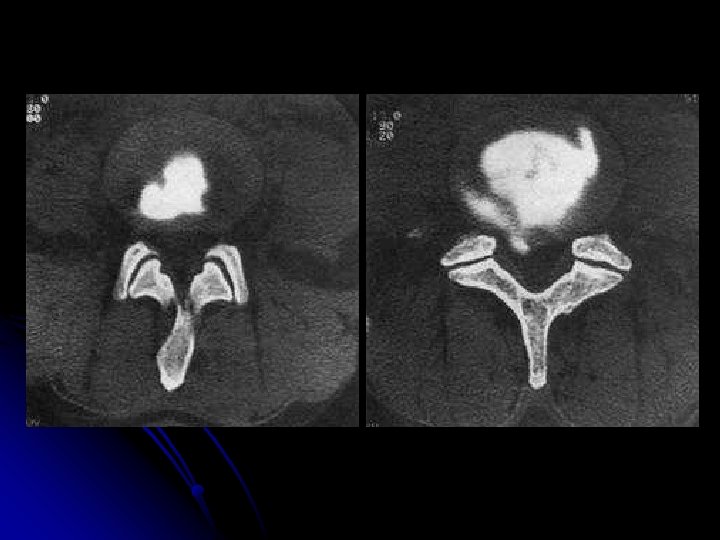

DISCOGRAPHIE lombaire+++

DISCOGRAPHIE